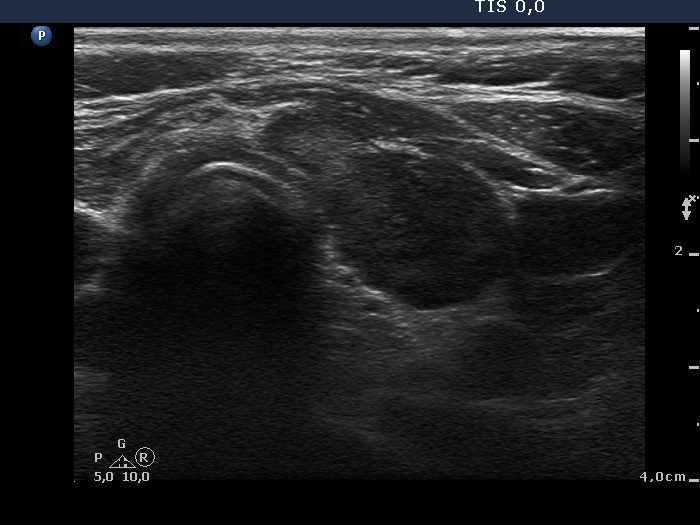

First examination - before surgery (first and second rows of images)

Ultrasonography. Both lobes were hypoechogenic and contained several hypoechogenic areas do not corresponding to nodules. The echogenicity index was 20%. The vascularization was a bit increased.

Aspiration cytology was performed from one of the hypoechogenic areas in the right thyroid and resulted in benign, hormonal atypia.